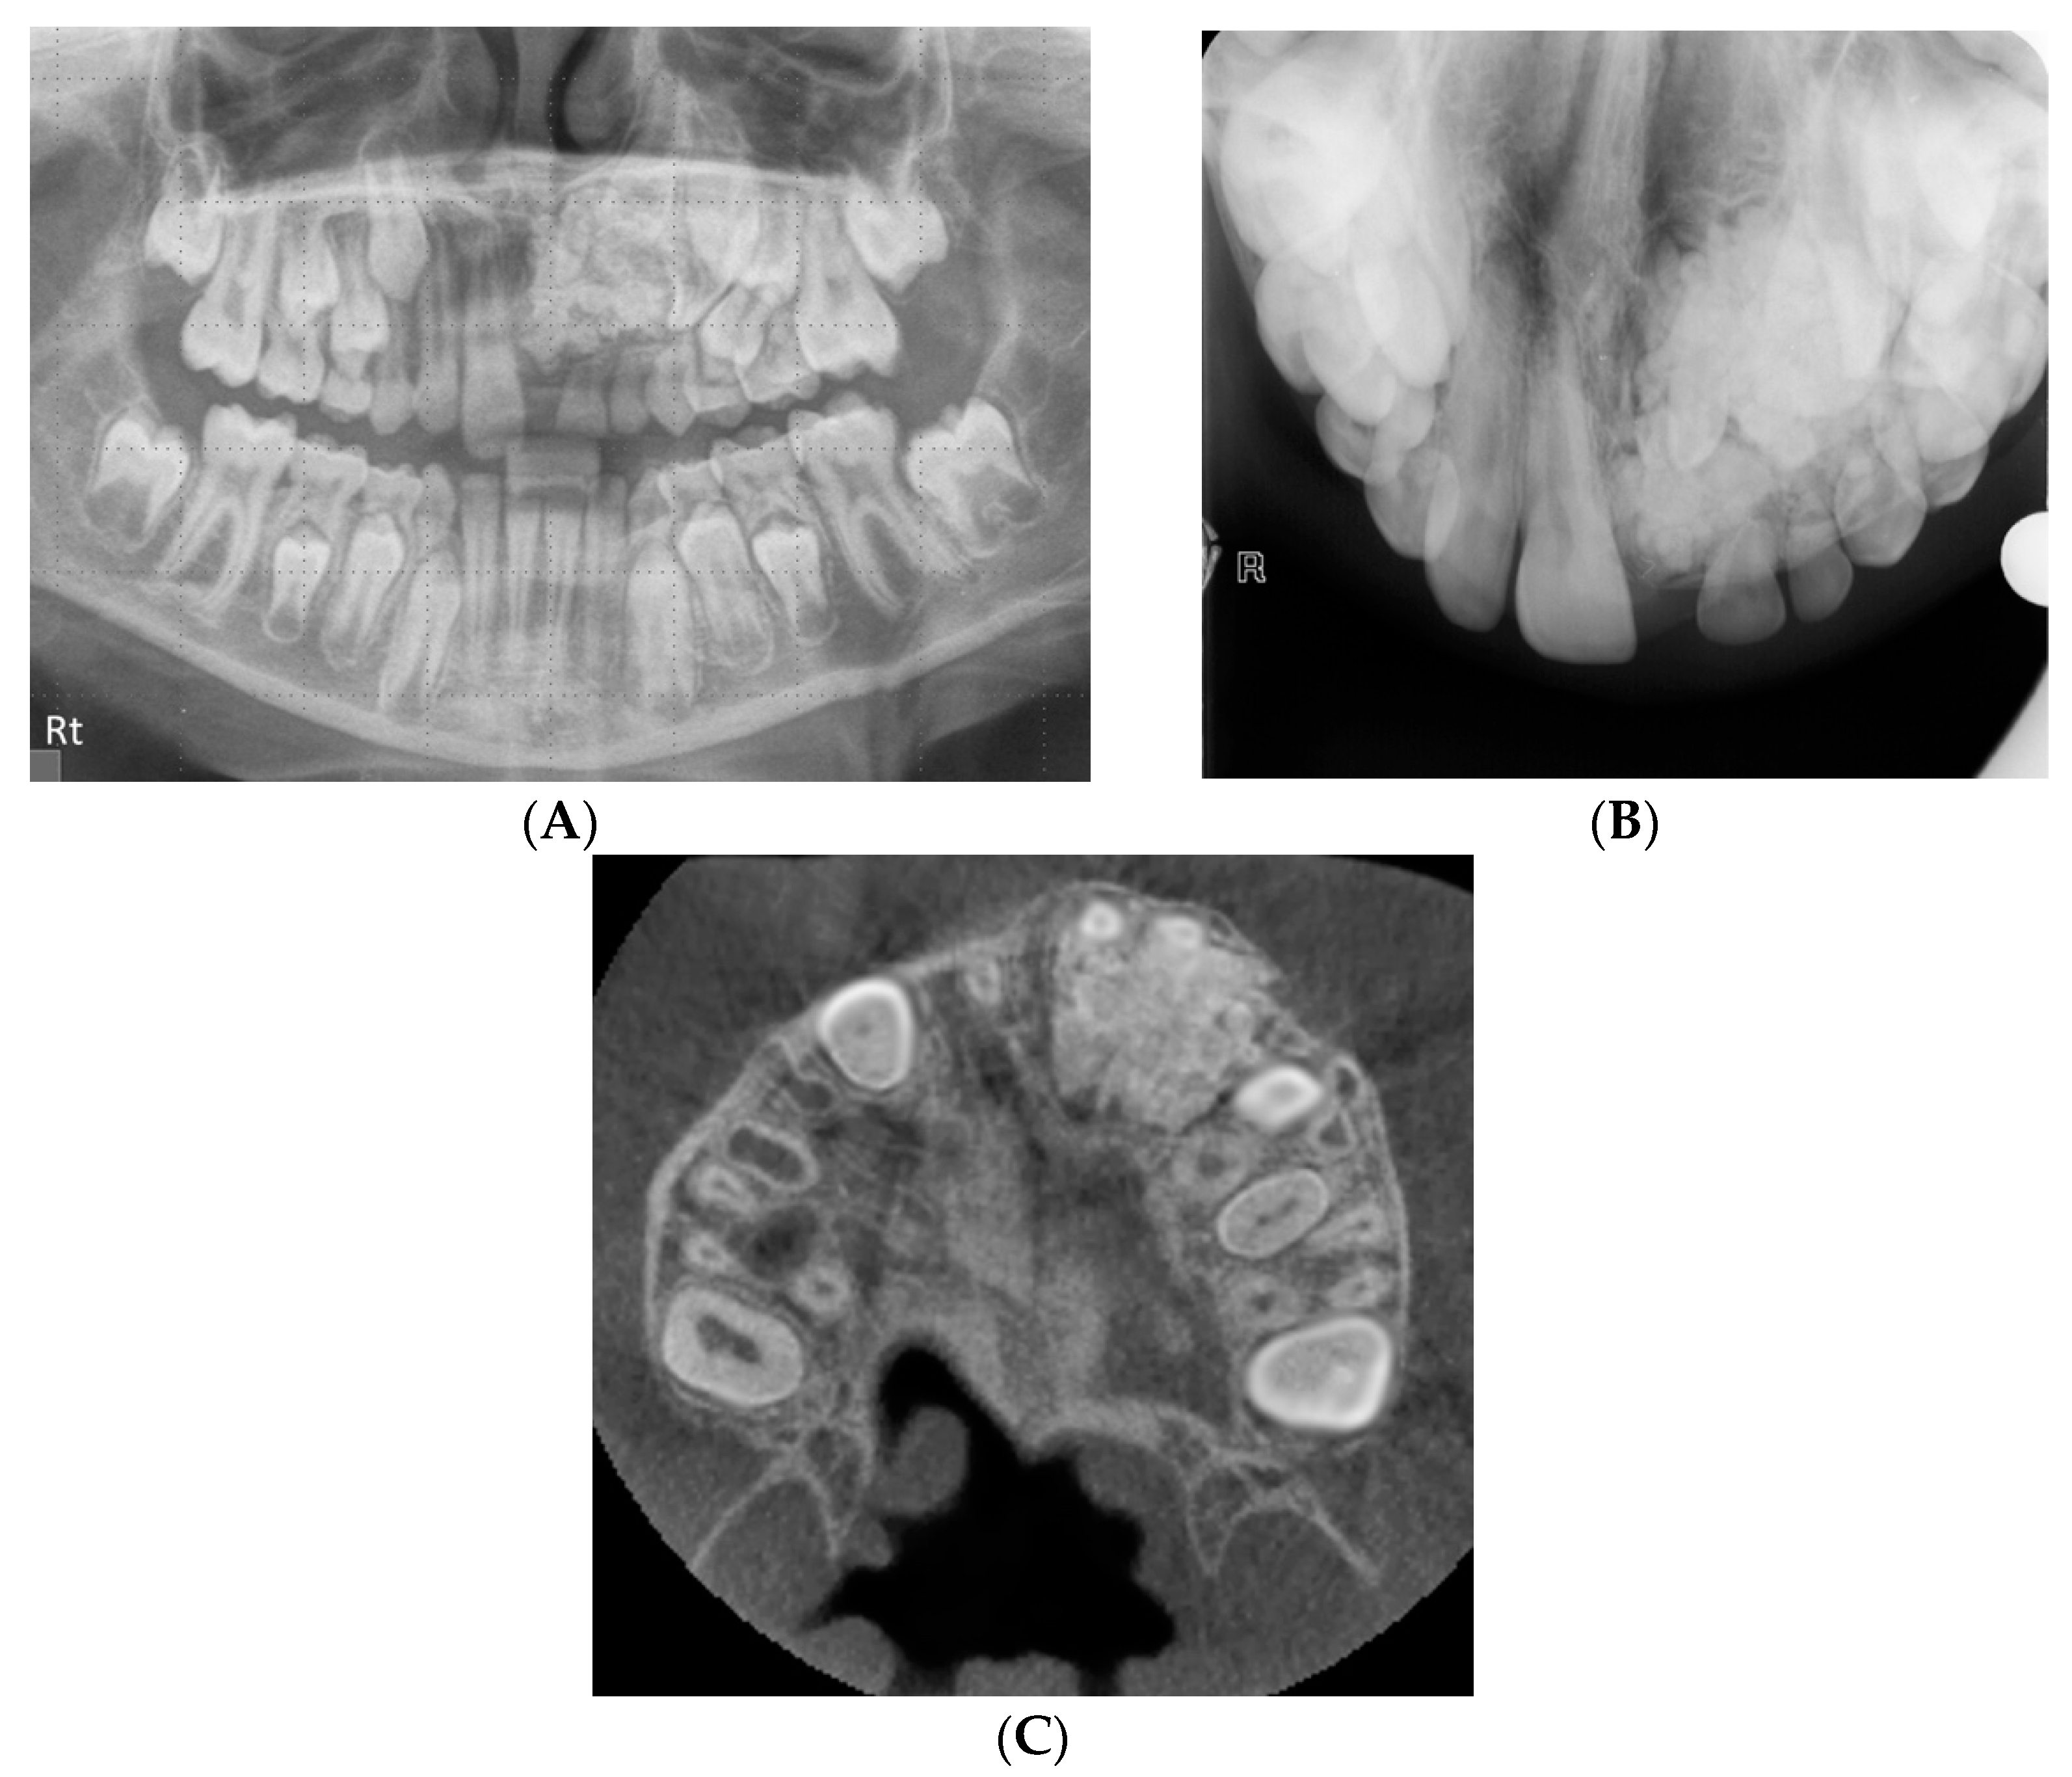

The CBCT scan reports proved invaluable in assisting the clinicians confirm and guide the surgical treatment plan and thus justified the radiation dose, as demonstrated in Figure 2. The panoramic and upper standard occlusal radiography aided in the detection of a mixed complex-compound odontome in the left anterior maxilla, but provided insufficient information for management and treatment planning. The capacity of CBCT to provide three-dimensional multiplanar reconstruction of the region of interest allows visualisation of the anatomical structures possible from all viewpoints. This aided in the surgical excision of the odontome to minimise any damage to adjacent teeth and structures.

Figure 2.

(A) Panoramic radiograph showing a mixed complex-compound odontome in the left anterior maxilla. (B) Upper standard occlusal view of the mixed complex-compound odontome. (C) CBCT axial view demonstrating the full extent of the odontome and its relationship to the teeth.